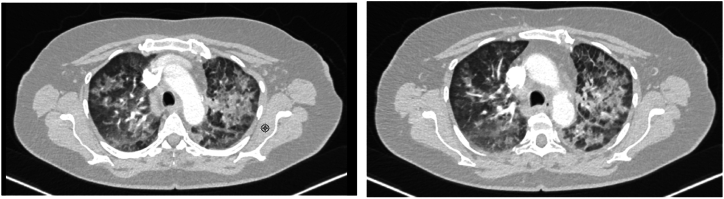

间变性淋巴瘤激酶酪氨酸激酶抑制剂(ALK TKIs)显示出强大的疗效,并彻底改变了ALK重排的非小细胞肺癌患者的治疗。ALK TKIs可产生副作用,有时甚至严重,如肺炎。我们报告一例ALK阳性晚期非小细胞肺癌患者在一线阿勒替尼治疗期间发生肺炎。由于没有确定肺炎的其他病因,患者接受皮质类固醇治疗并停用阿勒替尼。在快速的临床恢复和影像学检查后,患者开始使用布加替尼,没有复发的临床症状或肺炎的影像学表现。虽然需要进一步的描述,但我们的经验表明,对于一些服用ALK- tki后出现药物性肺炎的患者,改用第二种ALK- tki可能是一种安全的治疗选择。

We report a case of a patient with ALK positive advanced NSCLC who developed pneumonitis during treatment with first-line alectinib. With no alternative etiology of pneumonitis identified, the patient was treated with corticosteroids and discontinuation of alectinib. Following rapid clinical recovery and radiographic resolution of the opacities, the patient was started with brigatinib, with no recurrence of the clinical symptoms or radiographic findings of pneumonitis. While further descriptions are needed, our experience suggests that switching to a second ALK-TKI may be a safe therapeutic option in some patients who develop drug-induced pneumonitis on ALK TKIs.